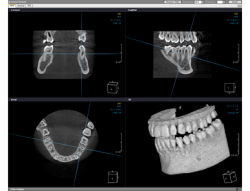

3次元画像解析システムで治療シミュレーションを行います。

歯科用CTにより3次元で撮影した画像を、PC上で画像解析し、歯の神経や骨の状態を細部まで分析します。

インプラント治療では、骨の深さや密度、インプラントを埋入する角度等が重要になります。

これらの情報をこのシミュレーションによって把握し、より安全で正確に治療進めることで、インプラント治療の成功率を高めています。